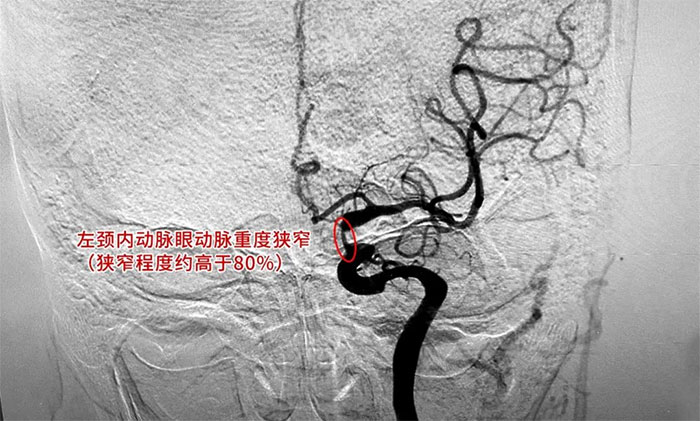

为进一步明确诊断并制定治疗方案,周君主任与医院学术副院长兼神经内科4A病区主任席刚明教授对患者病情开展了讨论评估,由席教授为患者进行DSA全脑血管造影检查,造影可见左颈内动脉岩骨水平段中度狭窄,左颈内动脉海绵窦段轻度狭窄,左颈内动脉眼动脉重度狭窄(狭窄程度约高于80%)。

▲ DSA检查影像